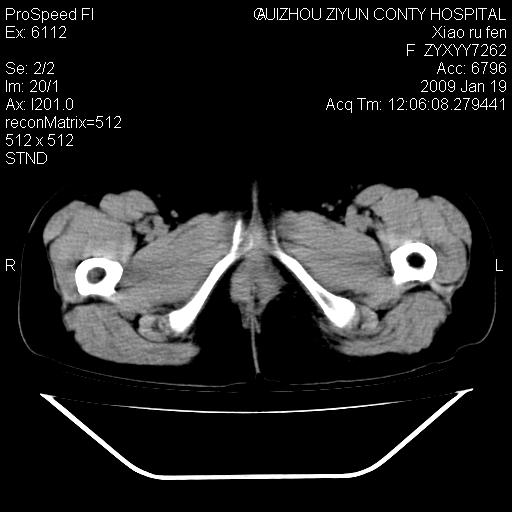

以下是引用随光逐影在2009-1-19 16:15:00的发言:[br]左侧臀部类似软组织密度肿块,性质待定(不排除肿瘤可能);建议行进一步检查。

以下是引用zbp537在2009-1-19 14:25:00的发言:[br]考虑两个诊断:1、皮脂腺囊肿伴感染。2、脓肿。[br]诊断依据:[br]1、肿块为低密度,边界较清,和皮肤相连,周围结构清晰,未见受累及。[br]2、诊断脓肿是因为其内密度不均匀,当然要结合病史,因为脓肿临床上肯定表现为红肿热痛,也希望楼主把病史提供全面些,这些便于讨论。

以下是引用zbp537在2009-1-19 14:25:00的发言:[br]考虑两个诊断:1、皮脂腺囊肿。2、脓肿。[br]诊断依据:[br]1、肿块为低密度,边界较清,和皮肤相连,周围结构清晰,未见受累及。[br]2、诊断脓肿是因为其内密度不均匀,当然要结合病史,因为脓肿临床上肯定表现为红肿热痛,也希望楼主把病史提供全面些,这些便于讨论。